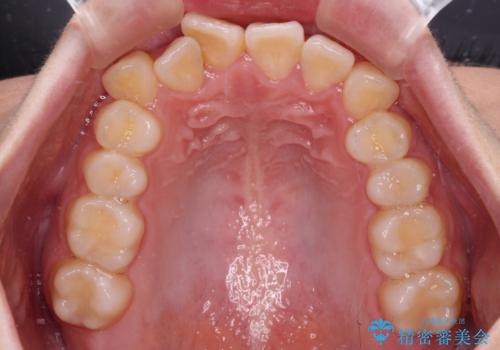

【モニター】八重歯を片側の抜歯矯正で治す メタルブラケット装置

- 八重歯とずれた正中を気にして来院された患者様です。

非抜歯矯正ではデコボコを解消することでより口元が突出する可能性があるため、上顎右右側の小臼歯1本の抜歯を行い、ワイヤー装置による矯正治療を行うこととしました。

正中位置を合わせるために、上顎臼歯部にアンカースクリューを埋入することとしました。